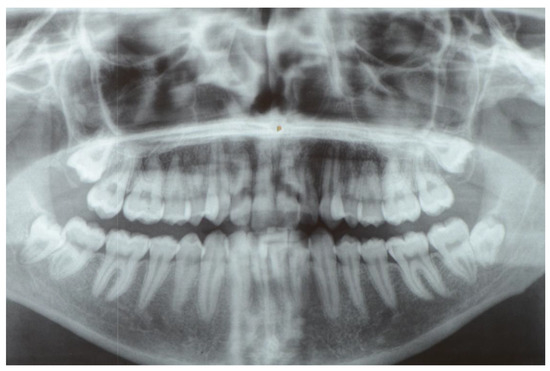

2. Materials and Methods

2.1. Study Design and Patient Selection